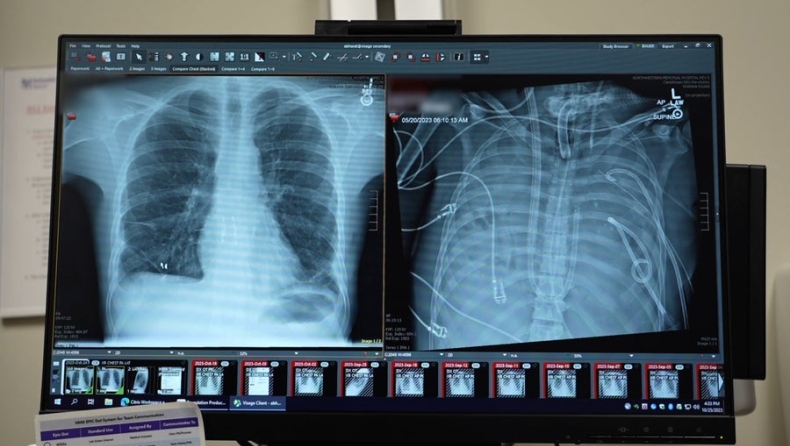

Το περιστατικό σημειώθηκε το 2023 στο Northwestern Memorial Hospital, όταν ο θωρακοχειρουργός Ankit Bharat κλήθηκε να παρακολουθεί έναν 33χρονο άνδρα με σοβαρή γρίπη, του οποίου η κατάσταση επιδεινωνόταν ραγδαία. Ο ασθενής είχε προσβληθεί από δευτερογενή λοίμωξη με Pseudomonas -ένα από τα πιο επικίνδυνα νοσοκομειακά μικρόβια- ενώ οι πνεύμονές του είχαν γεμίσει υγρό και πύον. Ταυτόχρονα, παρουσίαζε νεφρική ανεπάρκεια και η καρδιά του μόλις που λειτουργούσε.

Όταν η καρδιά του ασθενούς σταμάτησε και επανήλθε οριακά, η ιατρική ομάδα πήρε μια απόφαση χωρίς προηγούμενο. Σχεδίασαν και εφάρμοσαν ένα αυτοσχέδιο σύστημα «τεχνητών πνευμόνων», το οποίο παρέκαμπτε πλήρως το φυσικό όργανο. Το σύστημα αντλούσε αίμα από τη δεξιά πλευρά της καρδιάς, το οξυγόνωνε έξω από το σώμα και το επανέφερε στην αριστερή πλευρά, επιτρέποντας την κυκλοφορία του σε όλο το σώμα.

Ο ασθενής μπήκε στη λίστα μεταμόσχευσης και μέσα σε λίγες ώρες βρέθηκε κατάλληλος δότης. Η επέμβαση πραγματοποιήθηκε επιτυχώς και, έπειτα από εβδομάδες νοσηλείας, ο άνδρας πήρε εξιτήριο. Σήμερα, περισσότερο από δύο χρόνια αργότερα, «είναι σε εξαιρετική κατάσταση», σύμφωνα με τον γιατρό του.